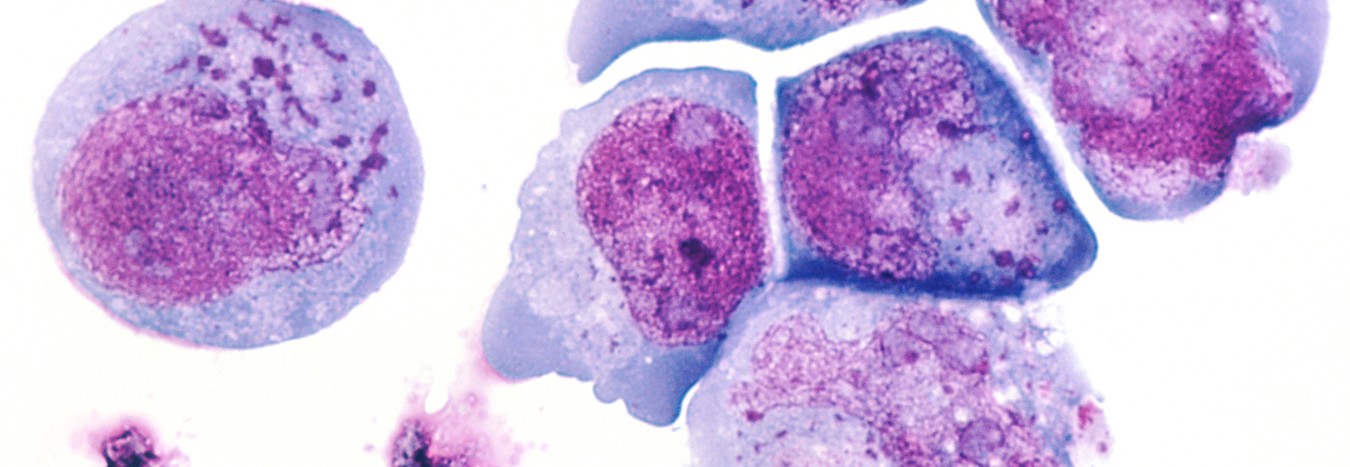

La explicación está en la mutación genética que tienen algunas células dañadas. Así, mientras que la mayoría de las que son cancerosas son aniquiladas gracias a la terapia, otras no sólo se muestran resistentes, sino que siguen multiplicándose de forma descontrolada.